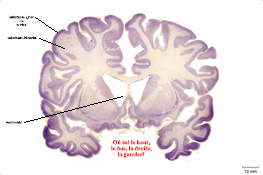

anatcerv25.jpg